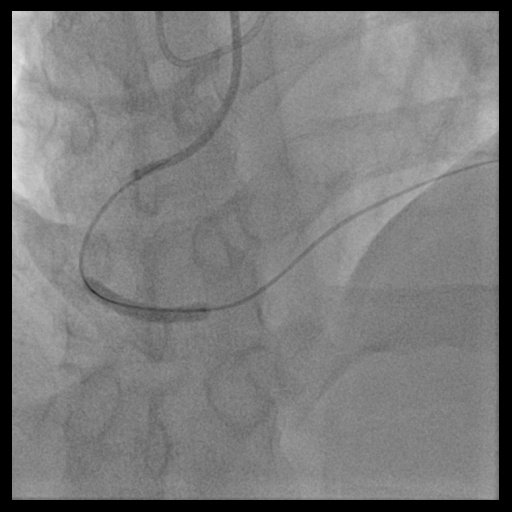

In anticipation of a high thrombus burden, intracoronary Tirofiban was given to mitigate thrombotic risks. The Terumo 6 Fr in 5 Glidesheath Slender was exchanged for a 7 Fr in 6 Glidesheath Slender to accommodate larger catheters while preserving radial artery access. Using a 7 Fr SAL 1.0 guiding catheter (Medtronic, USA), the Fielder FC 0.014” × 180 cm wire (ASAHI Intecc, Japan) was advanced to the distal RCA. Despite GuideLiner (Teleflex, USA) support, the Terumo Eliminate aspiration catheter could not advance beyond the mid-RCA. StentBoost imaging revealed the wire had wound along the aneurysmal vessel wall and passing through a previous stent’s strut. Attempts to reshape the wire tip for re-entry into the stent center were unsuccessful. Although stent crushing was considered, navigating the wire through the stent without damage was prioritized. An Euphora balloon (2.0 × 20 mm) was inflated at 2 atm to seal the gap between the stent and vessel wall, enabling the passage of a Runthrough NS Floppy wire into the distal RCA. IVUS confirmed the wire’s position within the stent, which remained intact. The wire was exchanged for an ASAHI Sion Blue Extra-support wire with a Caravel microcatheter. Thrombus aspiration was completed using the Eliminate catheter. Post-dilatation was performed with a Conqueror NC balloon (4.00 × 20 mm, APT Medical), followed by NC Emerge and Accuforce balloons (4.5-6.0 mm). IVUS confirmed excellent stent apposition, and TIMI 3 flow was achieved.

Case Summary